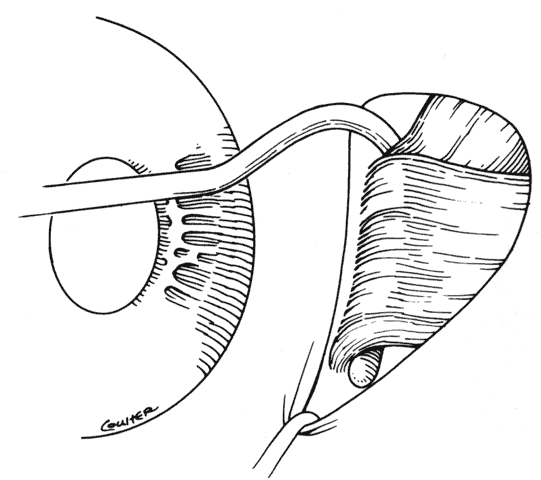

When approaching the superior and lateral rectus muscles that have had previous surgery, care should be taken to identify the superior oblique tendon and the inferior oblique muscles respectively. One should carefully free up attachments of these structures to the rectus muscle so that a normal anatomic relationship between the rectus and oblique muscles can be re-established. Frequently, the lateral rectus muscle will have adhesions to the orbital surface of the inferior oblique muscle as it passes underneath the lateral rectus. There is a propensity for the inferior oblique muscle to be drawn up into the insertion during resection procedures.37 When this occurs, the inferior oblique and lateral rectus muscle must be separated, and the inferior oblique muscle should be repositioned into its normal anatomic position (Figs. 30 through 33).

Fig. 30. To break posterior adhesions between the rectus muscle and the sclera, a second Jameson hook should be carefully pushed posteriorly along the belly of the rectus muscle. These adhesions are usually broken with little effort. If the adhesions resist blunt separation, a suture should be placed through the tendon and the muscle cut free from the insertion. With a malleable retractor, the adhesion is identified and then cut.

Fig. 31. The inferior oblique muscle has been incorporated into the insertion of the right lateral rectus.

Fig. 32. Sharp and blunt dissection is used to “free up” the inferior oblique muscle from the scleral side of the lateral rectus.

Fig. 33. If the dissection needs to be carried beyond the equator, care must be exercised to avoid avulsing or cutting a vortex vein. If this happens, a moderate hemorrhage will occur.